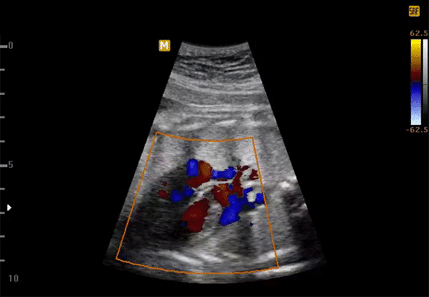

Ультразвуковая допплерография (допплерометрия, УЗДГ) – это разновидность УЗИ. Она позволяет оценить функционирование плаценты и кровотока в маточных артериях, диагностировать работу сердца ребенка и оценить общее состояние плода. С помощью УЗГД можно на ранней стадии выявить сужение сосудов матки, которое приводит к нарушению кровотока плаценты, и, как следствие, гипоксии плода. Во время допплерографии проводится исследование крупных и мелких сосудов, измеряется скорость кровотока в каждом из них.

Особой подготовки к проведению допплерометрии не требуется, не обязательно приходить натощак или пить много воды, на результаты это не повлияет. Внешне процедура не отличается от обычного УЗИ – на живот беременной женщины наносится специальный гель, затем врач водит по поверхности кожи специальным датчиком – через него изображение после обработки выводится на экран. Разница исследований именно в датчике – допплер реагирует на движение кровяных клеток, позволяя оценить скорость кровотока, его направление, ширину сосудов. Допплерография помогает вовремя выявить нарушения и определить степень их развития. Данные параметры позволяют обнаружить: